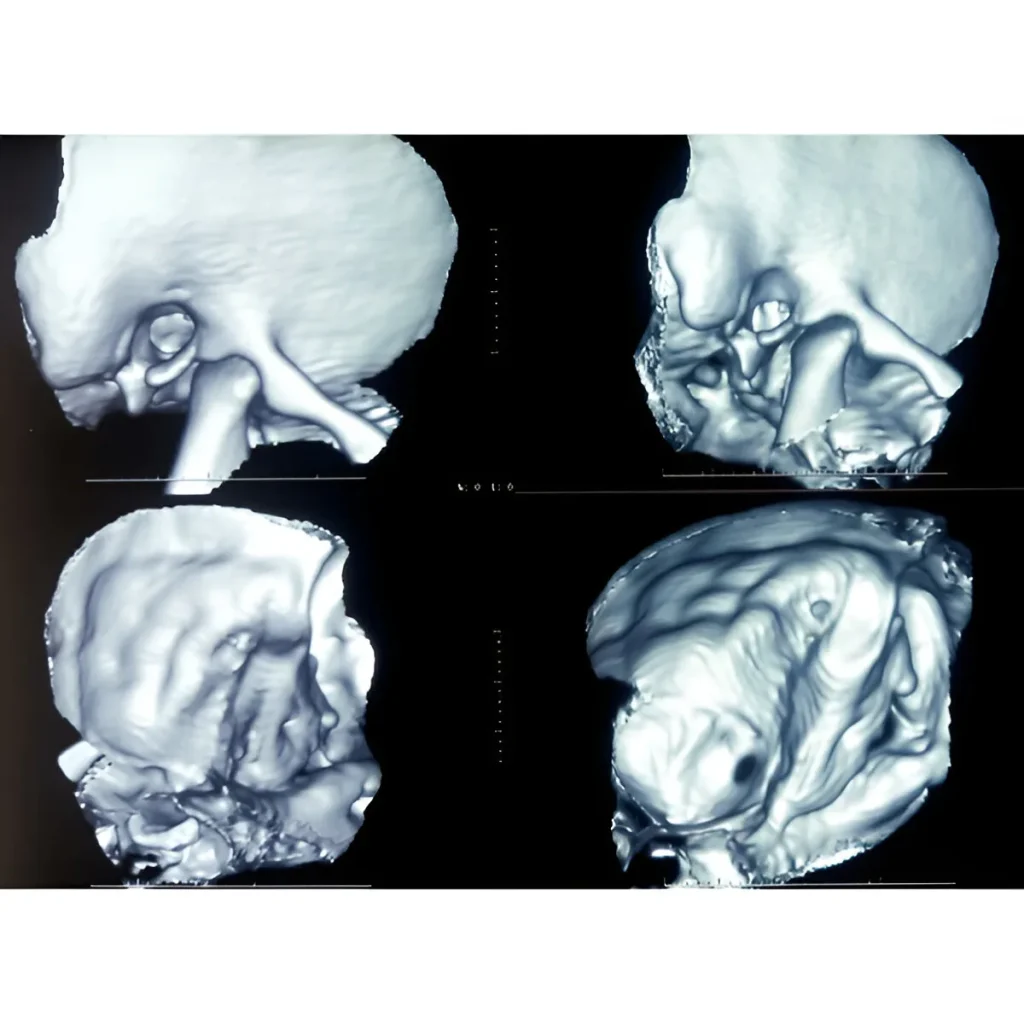

3D CT Scan with VRT Imaging in Navi Mumbai | Henotic Diagnostics

Looking for a 3D CT Scan with VRT Imaging in Kharghar? At Henotic Diagnostics, Kharghar, we provide high-resolution 3D CT scans with Volume Rendering Technique (VRT) for clear visualization of bones, blood vessels, and soft tissues. Moreover, this advanced imaging technique offers precise details, which helps in diagnosing fractures, tumors, vascular diseases, and supports complex surgical planning. In addition, our multi-slice CT scanner ensures accurate images with minimal radiation. Therefore, patients from Kharghar, Panvel, Belapur, Nerul, Vashi, and Navi Mumbai can rely on us. Book your 3D CT Scan today for superior diagnostic accuracy!